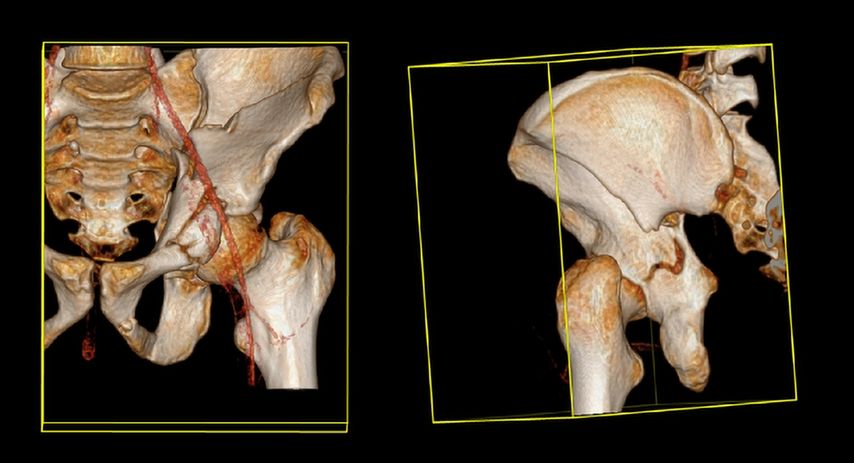

Die Mehrheit der Herausforderungen bei der Behandlung der Fragilitätsfraktur des Acetabulums überschneidet sich mit denen bei Beckenringfraktur. Ebenso wenig überraschend treten auch auf der anderen Seite des Hüftgelenkes ähnliche Komplikationen und eine Reduktion der Lebenserwartung wie bei hüftnahen Oberschenkelfrakturen auf. Im Unterschied zu den FFP gilt dieselbe Klassifikation für Hochrasanz- und Niedrigenergietraumata des Acetabulums nach Judet und Letournel. Der große Unterschied besteht jedoch in der Häufigkeitsverteilung. Aufgrund der meist einfachen Stürze mit Gewalteinwirkung über den Trochanter major betreffen die Fragilitätsfrakturen des Acetabulums meist den vorderen Pfeiler und die quadrilaterale Fläche. Entsprechend sind dislozierte Frakturen eine Domäne der offenen Operationsverfahren und der Hüftendoprothetik. Der Stellenwert der minimalinvasiven Stabilisierung nicht dislozierter Acetabulumfrakturen und der Stabilisierungen in Fehlstellung ist wissenschaftlich nicht geklärt. Jedoch gibt es zunehmende Literatur über das sogenannte „fix and replace“, bei dem eine Osteosynthese eines Pfeilers mit einer primären Totalendoprothese in einer Operation kombiniert wird (Abb. 2).

Abb. 2: „Fix and replace“ mit Osteosynthese und Hüfttotalendoprothese in der selben Operation bei geriatrischer Acetabulumfraktur mit Impressionsfraktur des Doms

Die „Fix and replace“-Behandlungsoption ist gerade für Zwei-Pfeiler-Frakturen interessant, da bei dieser häufigen geriatrischen Frakturform aufgrund der vorliegenden sakroiliakalgelenksnahen Beckendiskontinuität selbst durch gängige Revisionspfannen nicht immer eine Belastungsstabilität erreicht werden kann (Abb. 3).

Im Gegenzug dazu wird in der Literatur auch eine minimalinvasive offene Osteosynthese beschrieben, wobei man auf ausgedehnte Repositionsmanöver mit dem damit verbundenen Blutverlust verzichtet. Dadurch werden zum Teil verbliebene Fehlstellungen akzeptiert bzw. wird durch postoperative Mobilisierung eine sekundäre Dislokation in Kauf genommen, um eine postoperative Vollbelastung zu ermöglichen. Eine entsprechende Operationstechnik über einen Stoppa-Zugang und mit Plattendesign mit Abstützung der quadrilateralen Fläche wurde durch Culemann 2023 anschaulich beschrieben.12 Bei geschwächter Knochenqualität ist neben dem Plattendesign mit medialer Abstützung an der quadrilateralen Fläche auch das Augenmerk auf eine stabile Verankerung zu legen. Die infraacetabuläre hintere Pfeiler-Schraube, welche meist um die 100mm Länge aufweist, ist hierbei sehr empfehlenswert (Abb. 2 und Culemann 202312).